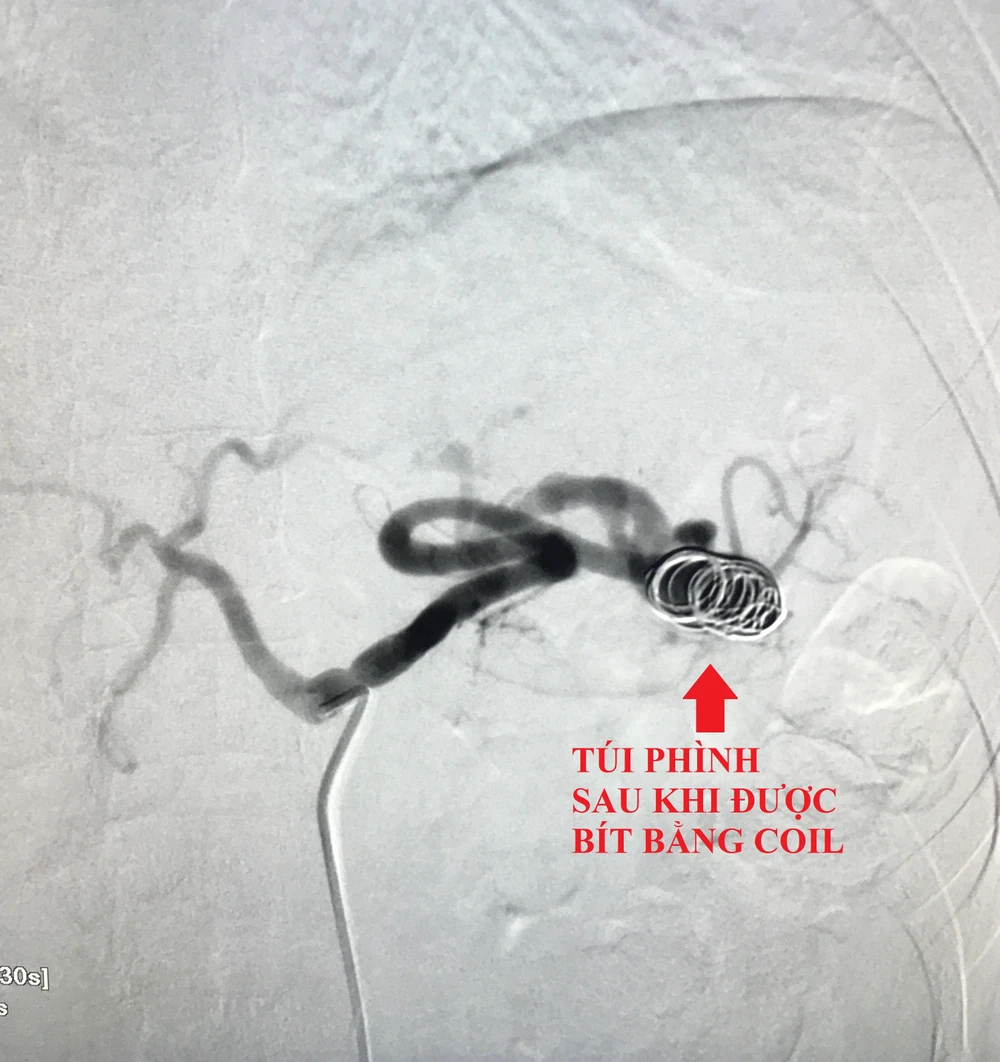

Bệnh nhân được lựa chọn can thiệp bằng ống thông với hỗ trợ của hệ thống chụp xóa nền mạch máu DSA qua đường mạch máu nhằm tránh nguy cơ phẫu thuật phải cắt lách.

Theo đó, các bác sĩ mở một lỗ nhỏ ở động mạch đùi, qua đó luồn ống thông vô đến lỗ động mạch lách, sau đó đến vị trí túi phình và thả 3 coil (vòng xoắn kim loại) bít hoàn toàn túi phình. Bệnh nhân hết đau tức vùng bụng và được xuất viện sau 2 ngày.

Túi phình động mạch lách sau khi được bít bằng coil. Ảnh: BVCC